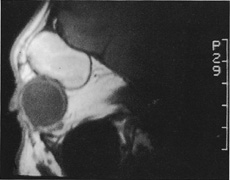

Valuable information about the nature and extent of an orbital pathologic process is provided by imaging studies such as computed tomography (CT) scan, magnetic resonance imaging (MRI), and orbital echography. Better spatial resolution, ready accessibility, and lower cost make CT the preferred choice for orbital imaging in most cases. Orbital fat provides a natural contrast between most adjacent orbital structures on CT scanning, and orbital bones are visualized well. Computed tomography is essential for evaluation of the orbital bones because they cannot be imaged with MRI. Direct coronal or sagittal images are important to identify the relationship of a lesion to the optic nerve so that the surgical approach can be planned to avoid traversing the optic nerve (Fig. 1).

Fig. 1. A. Axial CT scan demonstrating a large, well-encapsulated lesion in the orbital apex. Coronal (B) and sagittal (C) scans demonstrate that the mass lies inferior and medial to the optic nerve within the intraconal space. This information is useful in planning the surgical approach to the mass, which should avoid traversing the optic nerve.